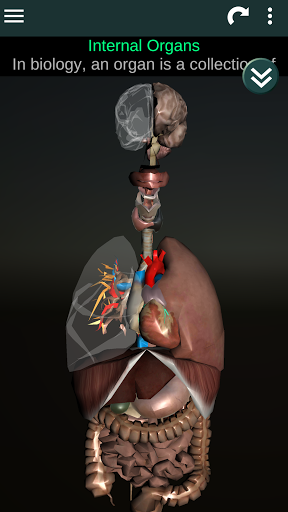

Menampilkan model anatomi 3D dari organ utama tubuh manusia dan penjelasannya masing-masing.

Apa yang ada di aplikasi?

* Sistem pencernaan, termasuk lambung, usus kecil, usus besar, dan animasi sistem ini.

* Sistem pernafasan, yang meliputi trakea, bronkus, paru-paru dan animasi sistem ini.

* Otak, yang meliputi otak, otak kecil, dan batang otak.

* Jantung, yang meliputi atrium, ventrikel, aorta, dan animasi organ ini.